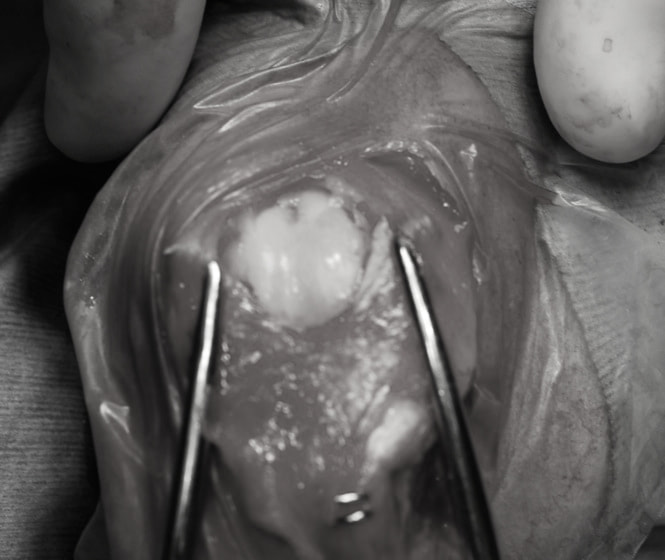

■ 症例20 ポメラニアン 8ヶ月 1.8kg

左右膝蓋骨脱臼 グレードⅢ

2ヶ月前から間欠的跛行が認められ、両膝の膝蓋骨脱臼整復術を行った。

手技は縫工筋及び内側広筋の解放、脛骨粗面の外側転位、滑車ブロック形造溝術、内外側関節包の縫縮を選択し実施した。

右側の膝蓋骨脱臼は上記手技で整復されたものの、左側はそれのみでは膝蓋骨が浮く様子が認められた。その為、PDS縫合糸にて膝蓋靱帯を1糸のみ縫合し、靱帯の縫縮を行った。

膝蓋骨脱臼は膝関節における膝蓋骨の内外側の脱臼と定義されるが、時として単純な内外の脱臼ではなく、膝蓋骨が大きく前方に浮き上がるように脱臼する場合がある。特にトイプードルやポメラニアンといった犬種に多く認められる。

内側脱臼に加えて前方への浮き上がりを矯正する為に、従来より脛骨粗面転移により膝蓋靭帯を外方と下方に引っ張り、固定する方法を選択する。膝蓋骨の前方への浮き上がりが軽度の場合は、従来法ではなく関節包の縫縮で対応していた。しかし、一部の症例で膝蓋骨の動きが悪くなり伸展機構が円滑に機能せずロボット様歩行になるケースがあった。

その為、膝蓋靭帯自体を縫縮する方法を採用した。この方法により、膝関節の伸展機構を妨げず膝蓋骨の軽度の浮きを矯正することが可能となった。

本症例の経過は良好である